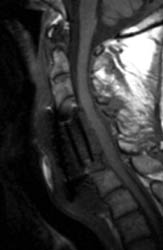

Sagittal T2 FSE (A), sagittal T1 pre (B) and post contrast

administration (C) show the graft with blooming artifact where the

plate exists anteriorly as well as the screw (lower portion of the image). The

susceptibility artifact of the screw shows its ventral positioning essentially

outside of the C7 vertebral body. Also, there is T2 hyperintense fluid

surrounding the surgical site with the graft material is now surrounded by

nonenhancing mixed signal intensity material, predominately hypointense on T1

and hyperintense on T2, possibly suggesting some blood products. There is

enhancement in both the anterior and posterior epidural spaces. The distal end

of the fixation plate with the screw in the C6 vertebral body appears now

displaced anteriorly and there is significant prevertebral soft tissue swelling.

Also, this fluid- like material surrounding the bone graft appears to cause some

narrowing of the spinal canal, with some mild spinal canal stenosis.